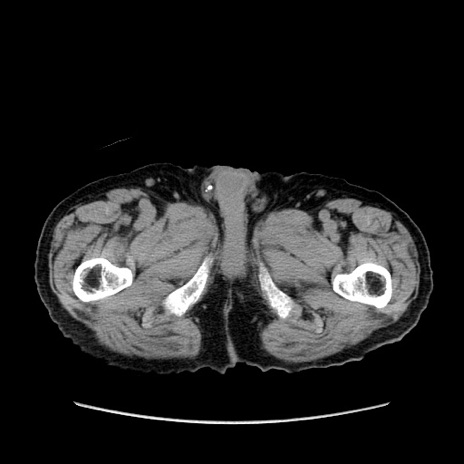

症例24(横断像)

【症例】80歳代男性

【主訴】左側腹部痛、嘔吐

【現病歴】本日早朝より左腹部に痛みあり。昼頃嘔吐認めたため、救急要請。

【既往歴】直腸癌(Mile手術)、胆摘

【身体所見】意識清明、BT 35.9℃、BP 221/93mmHg、SpO2 97%(RA) 、腹部:左ストーマ周囲に限局性の腹部膨隆あり。 膨隆部自発痛・圧痛あり・軟。

【データ】WBC 7700、CRP 0.09